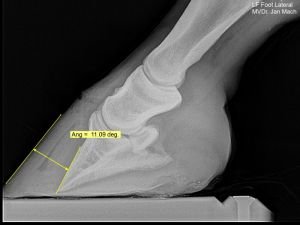

Během prvního přednáškového dne se Prof. Pollitt věnoval nejen anatomii a fyziologii kopyta, ale také seznámil posluchače se zobrazovacími metodami (RTG a angiografie) vhodnými k diagnostice laminitidy. Ve dni druhém se pak zaměřil na kopyto postižené laminitidou, její jednotlivé fáze, možnosti léčby a prezentoval zajímavé případové studie. Obsáhlé prezentace byly doplněny jeho vlastními výzkumy a praktickými ukázkami. Akce se zúčastnilo celkem 207 posluchačů z řad veterinárních lékařů, studentů a podkovářů, kteří díky on-line aplikaci Sli.do položili během víkendu více než 50 dotazů. Všichni poté odcházeli plni nových informací a s pocitem příjemně stráveného víkendu s kolegy.

Za odbornou pomoc a ilustrační fotografie velice děkuji MVDr. Jánu Machovi.